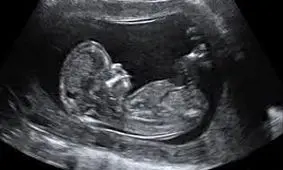

گروهی از محققان در آخرین مطالعه خود علت لگد زدن جنین در رحم مادر که سالها همانند معمایی برای دانشمندان بود را توضیح دا…